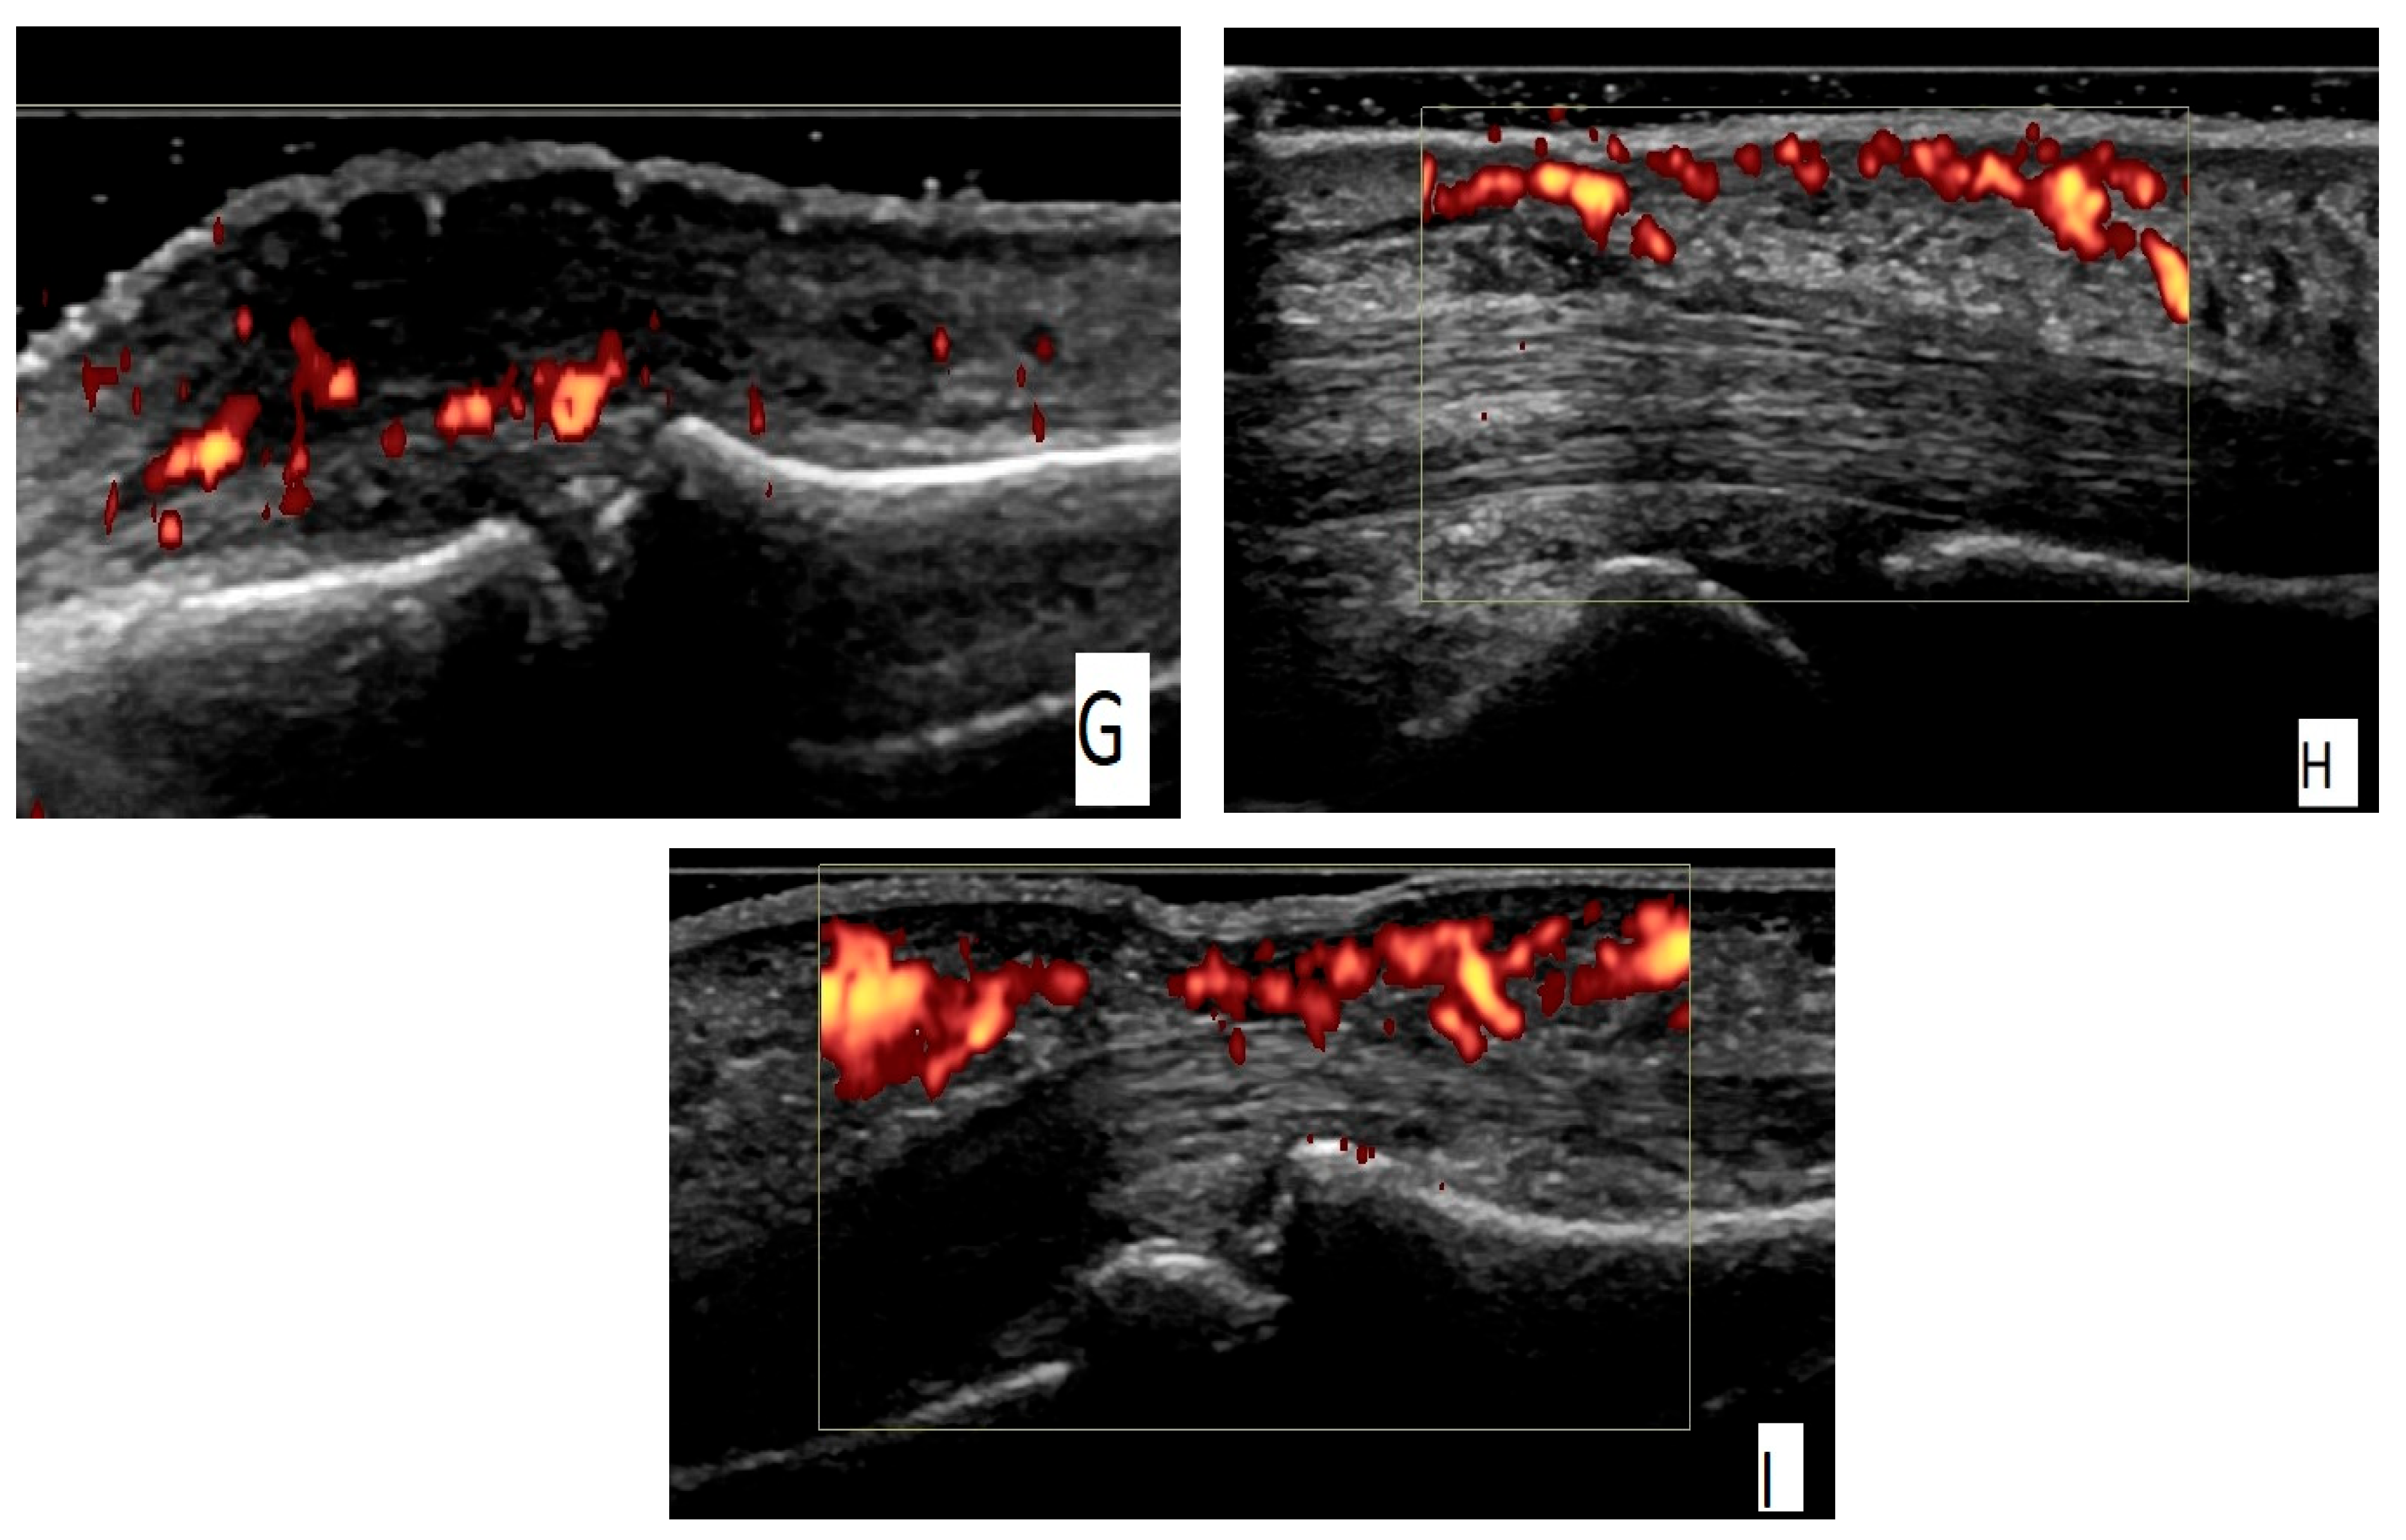

3.3. Imaging Assessment

3.3.2. Musculoskeletal Ultrasound (MSUS)

- Sapundzhieva, T.; Karalilova, R.; Batalov, A. Hand ultrasound patterns in rheumatoid and psoriatic arthritis: The role of ultrasound in the differential diagnosis. Rheumatol. Int. 2020, 40, 837–848. [Google Scholar] [CrossRef] [PubMed]